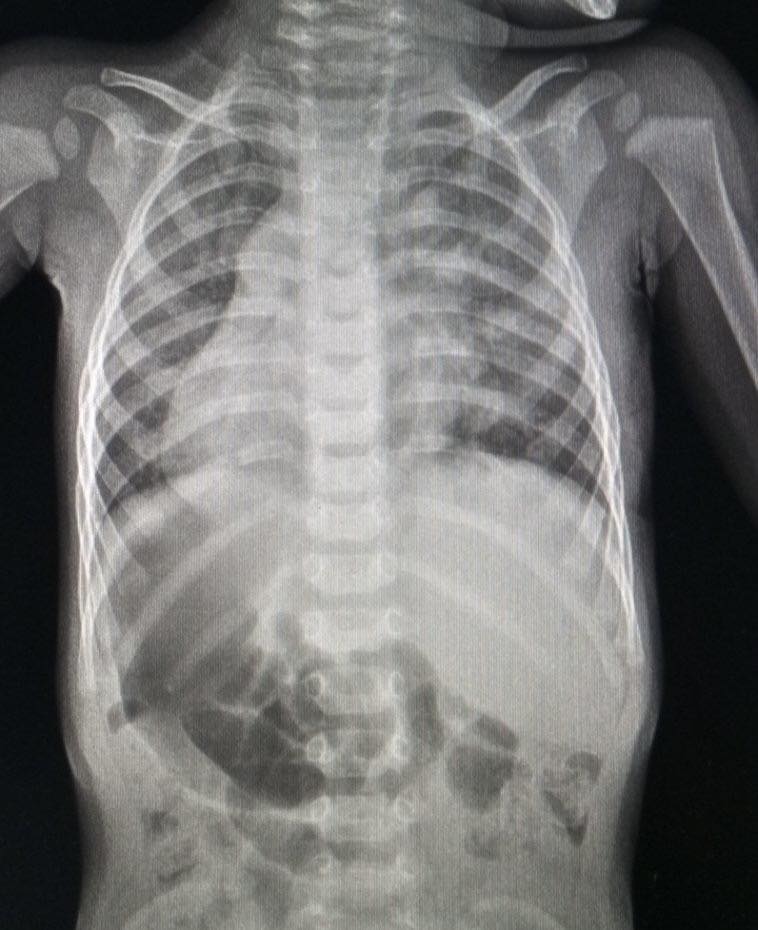

Як повідомили у Дитячій лікарні Святого Миколая, під час планового огляду у 9 місяців у дитини виявили серцеву ваду, дефект міжпередсердної перегородки з частковим аномальним дренажем легеневих вен. Через складну анатомію випадок вимагав високоточного хірургічного втручання.

Кардіохірурги провели операцію малоінвазивним методом — через невеликий розріз під пахвою. Під час втручання дефект перегородки був закритий, а кровотік легеневих вен перенаправили у ліве передсердя.